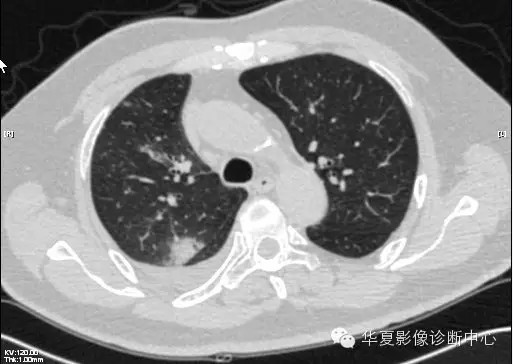

【病例学习】甲型H7N9禽流感一例

男性 63

发热咳嗽5天

2013-4-7CT进一步检查。

最终诊断:H7N9。